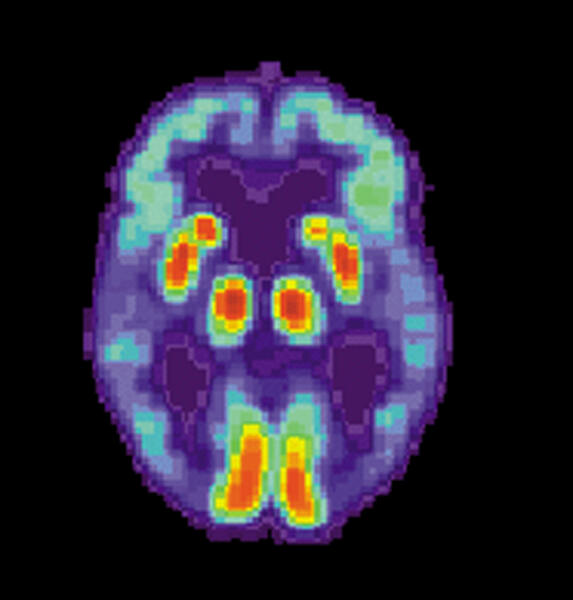

Диагностика обычно включает серию оценок, куда входят тесты на память и способность к познанию. Пациента проводят через серию тестов, чтобы выяснить, не вызваны ли проблемы с памятью другими причинами: физическим недомоганием или приемом лекарств. Есть и другие виды слабоумия, не имеющие отношения к болезни Альцгеймера. Также сканируют мозг и делают поясничные пункции, чтобы определить концентрацию амилоида — протеина, который является критерием наличия недуга.

Последние исследования показали, что этот протеин начинает накапливаться за 20 лет до появления симптомов грозной болезни в виде усиливающегося слабоумия. Развитие сканирующей техники, выявляющей амилоид на ранней стадии, позволяет выявлять будущих пациентов, включая тех, кто даже не подозревает, что его ждет.